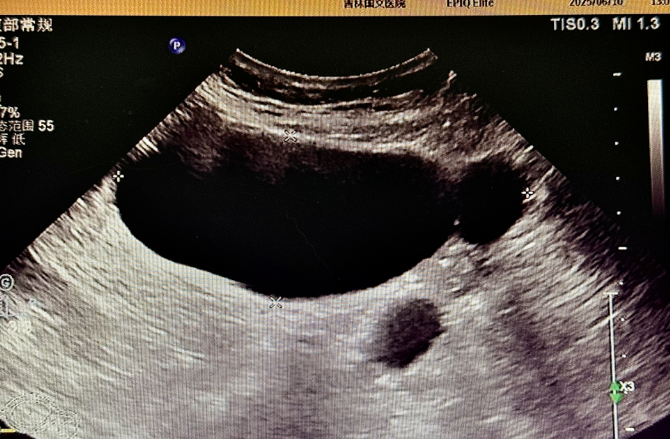

為精準(zhǔn)判斷病情,患者術(shù)前接受了多項影像學(xué)檢查:盆腔 MR 平掃顯示,腹腔內(nèi)存在囊性病灶,周圍伴有管狀影像,為病變定位提供了重要線索,下腹部 CT 進一步提示輸卵管擴張,腹盆腔內(nèi)可見低密度病灶,與 MR 結(jié)果相互印證,超聲檢查發(fā)現(xiàn)附件區(qū)有管狀無回聲結(jié)構(gòu),經(jīng)超聲科與婦科專家聯(lián)合會診,綜合分析后診斷為輸卵管積水。多項檢查數(shù)據(jù)的交叉驗證,如同為醫(yī)生裝上 “透視眼”,讓隱藏的病灶無所遁形,為后續(xù)手術(shù)方案的制定打下了堅實基礎(chǔ)。